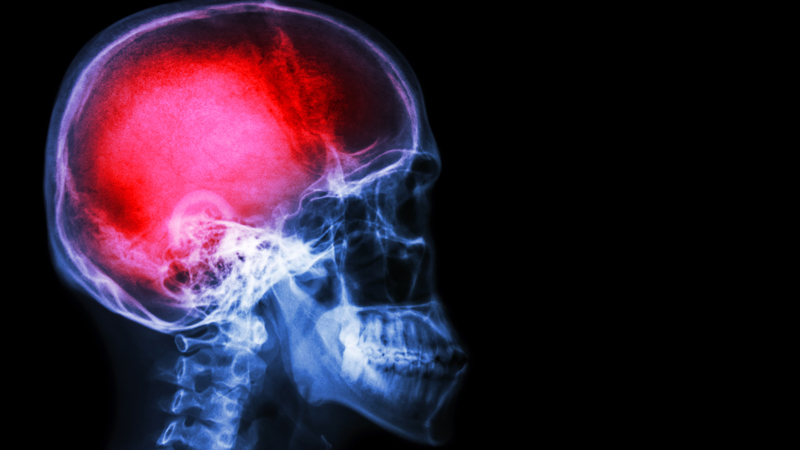

Central pain syndrome (CPS) is a neurological condition caused by an injury to the central nervous system, resulting in chronic pain. This syndrome can be caused by stroke, brain or spinal cord trauma, multiple sclerosis or tumors.